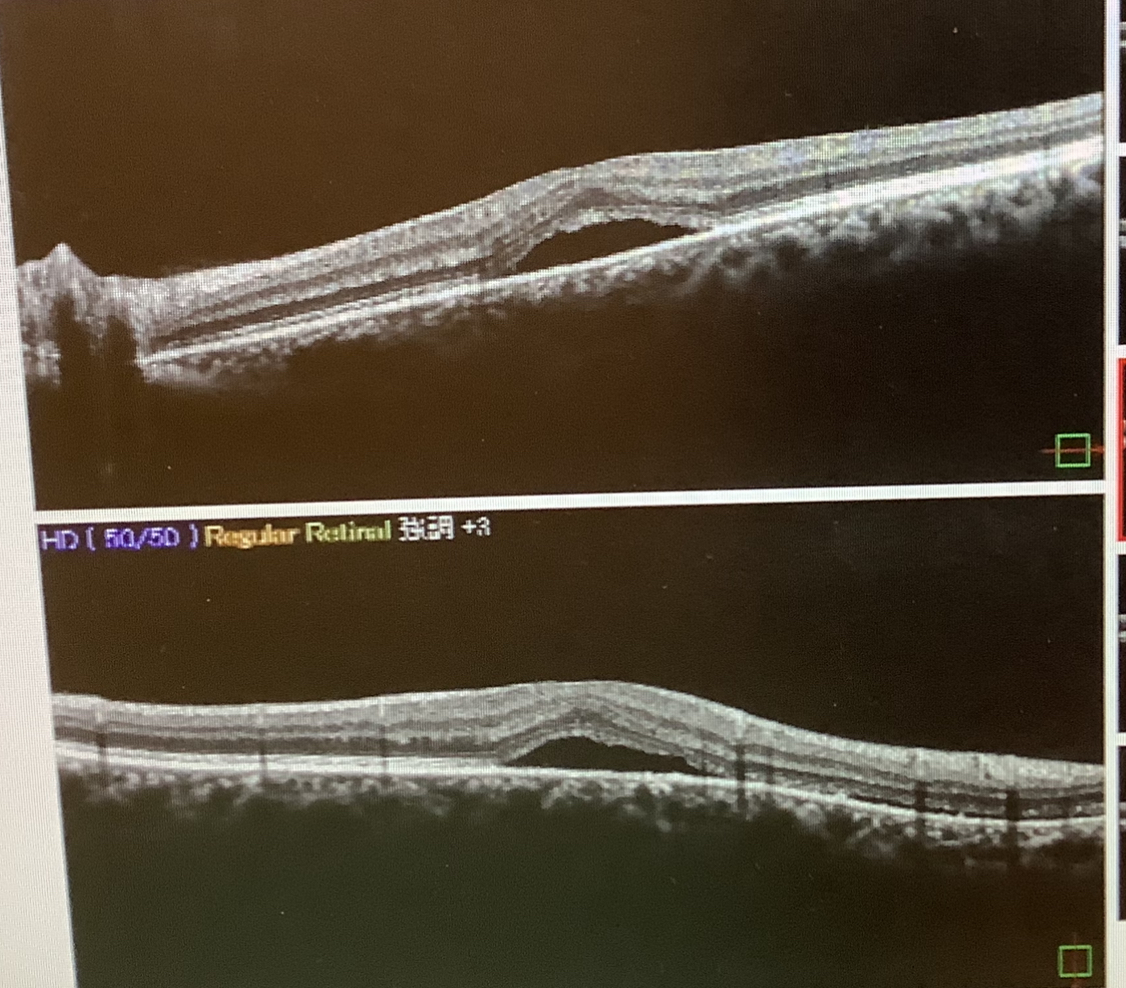

左眼の状態は、OCT検査で黄斑部の網膜の下に液体が貯留した“漿液性網膜剥離”(SRD)という所見が見られ、『中心性漿液性網脈絡膜症(CSC)』という病気と考えられました。40〜50代の男性によくみられる疾患で、網膜の下の脈絡膜という部分に何らかの炎症が起こり、脈絡膜側から液体成分が漏れ出すことで、網膜の下に水が貯まり、そのせいで、見えにくさ、歪み、物が小さく見える(小視症)などの症状が現れます。自然軽快することも多いですが、長引く場合や、一旦よくなってもまたぶり返す再発例では、より詳しい検査(蛍光眼底造影検査;FAG)を行い、水の漏れ出る場所を特定し、中心部からある程度、離れていれば、通常のレーザー治療を、中心部付近であれば(通常のレーザーではレーザーを照射したところが見えにくい暗点になってしまうので)、特殊な薬を点滴してからのレーザー治療(光線力学療法;PDT)が有効とされています。